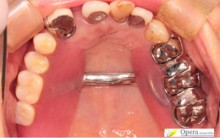

治療後

入れ歯のばねがかかるところにかぶせ物をしています。

入れ歯のばねがかかりやすいように、本来の歯の形と若干形を変えています。